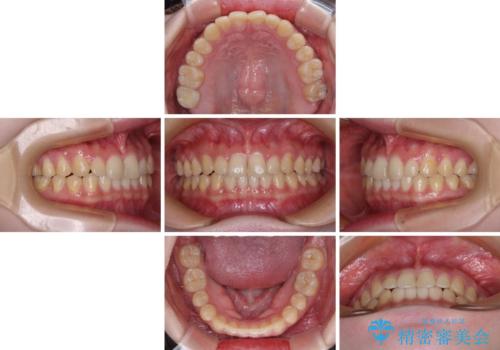

治療途中の奥歯と矯正治療の後戻り インビザライン・ライトによる矯正治療

クラウンはよりよい咬み合わせで装着したいため、インビザラインを1セット使用して概ね歯列を整えた時点で補綴治療を行い、その後仕上げの矯正治療を行いました。